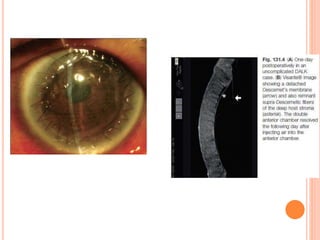

 Pseudoanterior chambers